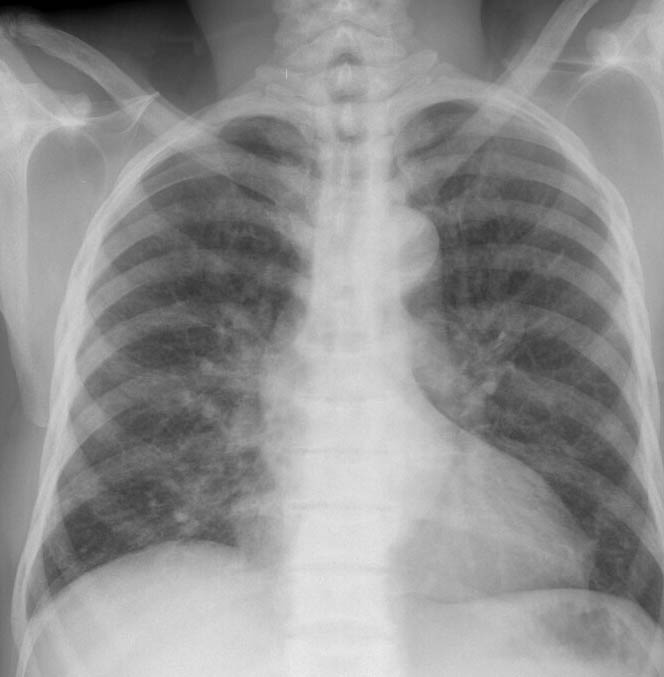

Sickle Cell 1 PA